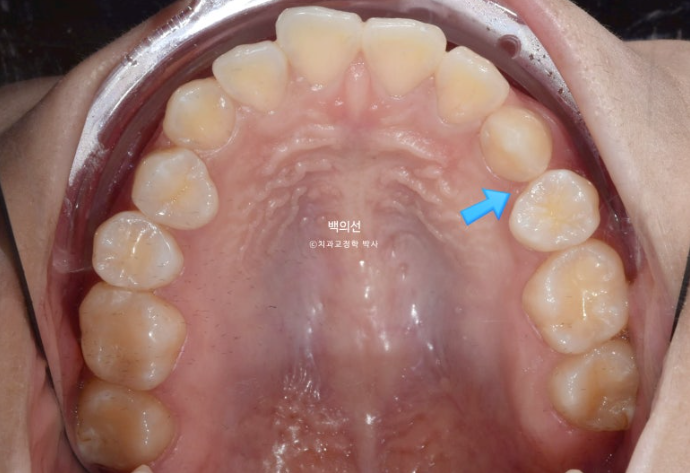

23.01

파란 화살표 자리에 있어야할 첫번째 작은어금니는 어디로 갔을까요?

네 매복이 되어있습니다.

매복치를 빼야만 교정이 가능한 경우도 많습니다. 하지만 이 매복치의 경우 매복깊이가 상당히 깊어 합병증이 우려가 되는 바 인접 치아들이 매복치를 건드리지 않게 치료계획을 세우기로 합니다. 다행히 매복치가 있는 좌측은 치아이동이 크게 필요하지 않습니다.

지난 번 말씀드렸듯이 작은어금니가 결손되어 없는 경우 치아 중심선이 그쪽으로 돌아가게 됩니다.

이 치아 중심선을 다시 중앙으로 끌어와 얼굴과 인중과 맞춰야 합니다.

이 환자분도 마찬가지입니다. 작은어금니가 매복된 쪽으로 앞니 중심선이 돌아가 있습니다.

아래에도 첫번째 작은어금니가 양쪽에 각각 결손되어 있네요. 그래서 공간들이 남아 치아들이 벌어져 있습니다.

태어날때부터 없는 치아를 선천적 결손치라고 합니다.

결론적으로 작은어금니 4개 중 3개가 입안에서 안 보이는 상태입니다. 2개는 결손, 한 개는 매복.

마침 돌출입도 보여서 이런 경우 유일하게 남아있는 작은어금니 1개만 빼면 작은어금니 4개 발치교정 한셈 치고 교정치료를 하면 좋습니다.

유일하게 잘 나와있는 작은어금니 1개를 아쉽지만 발치하고 인비절라인 치료에 들어갔습니다.